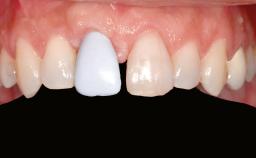

A 46-year-old woman was referred for treatment whose main complaints were mobility of her fixed partial dentures (right maxilla and left mandible) and periodontal bleeding during function. She also reported having taken systemic antibiotics to treat recurrent swelling in the area of the upper left molars. The patient had not seen a dentist for at least 2 years. She did not smoke and had no history of major systemic disease other than two minor orthopedic procedures some years back. The first-visit examination revealed poor plaque control, tooth mobility, periodontal disease, and a residual dentition widely associated with deep periodontal pockets.

| Prosthesis Type | FDP |

| Patient's Esthetic Expectations | Low | Medium | High |

| Lip Line | No exposure of papillae | Exposure of papillae | Full exposure of mucosa margin |